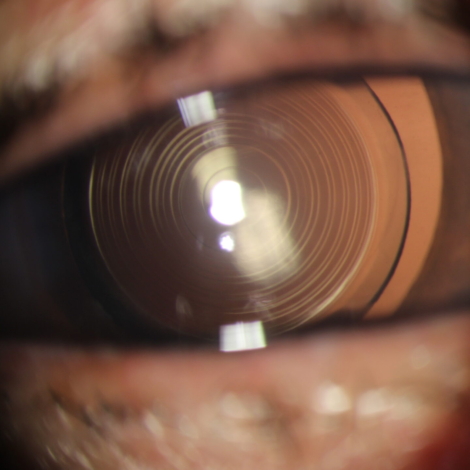

Foco na Troca do Cristalino com Finalidade Refrativa